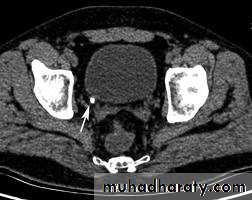

CT scans used in some hospitals during acute renal stone-Non contrast CT sensitively identify calculi and non opacified collecting system down to the level of obstruction. it has a sensitivity of 97% and specificity of 96% for detection of ureteral calculi